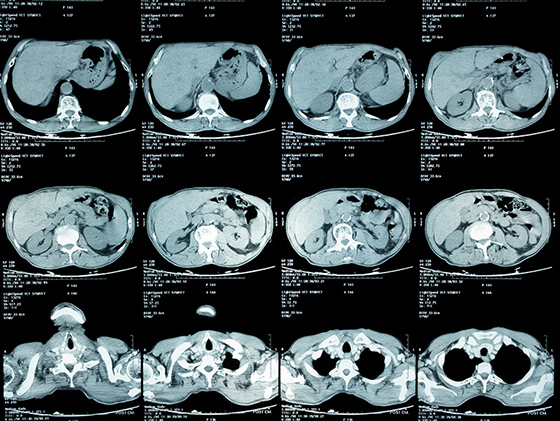

健康診断で再検査を言われ、精密検査をした結果、肺癌のステージⅣと言われました。その時は、もう何を言われたのか覚えてないですし、本当に頭が真っ白になりました。それまで、何気なく過ごしていた日常が全て失われ、何もかも嫌になりました。

それでも家族の支えもあり、少しずつ治療に前向きになり、抗がん剤治療などを受けましたが、残念ながら効果はありませんでした。副作用が強く、心も体も限界で抗がん剤治療をするくらいなら、もうステージⅣの悪性腫瘍が改善小さくなった画像を見て涙が止まりませんでした。死んでもいいと思っていました。

そんな時に私の友人から紹介され、松田先生に藁にもすがる思いで治療をお願いしました。私自身が治ることに諦めていましたが、松田先生は真摯に話を聞いてくれて、一生懸命治療をしてくれました。6ヶ月が経過した写真を見た時に、私でもわかるくらいにガンが小さくなっているのがわかりました。病院の先生の説明を聞きながら、涙を止まらなかったのを今でも覚えています。